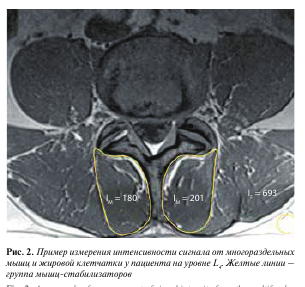

Изображения, полученные с помощью вышеописанной последовательности T1-vibe без жироподавления, открывали в программе InobitecPro в режиме мультипланарной реконструкции, где строились аксиальные срезы, параллельные в коронарной и сагиттальной проекциях нижним замыкательным пластинкам L3-, L4-, Ь5-позвонков (рис. 1). На построенных изображениях на всех 3 уровнях с помощью инструмента «ROI полигон» обводили многораздельные мышцы с обеих сторон, как показано на рис. 2 (вдоль границы остистого и суставного отростков, затем по фасции многораздельной мышцы), для оценки средней интенсивности сигнала и площади выделенной зоны. Кроме того, в режиме T1-vibe без жироподавления с помощью инструмента «ROI овал» измеряли среднюю интенсивность сигнала в жировой клетчатке слева от паравертебральных мышц (см. рис. 2).

Для объективизации полученных данных о наличии жировой ткани в структуре мышц нами был разработан и применен индекс жирового замещения (index of fat replacement, IFR): IFR = IM/IF, где IM — средняя интенсивность сигнала от зоны, соответствующей многораздельной мышце, IF — интенсивность сигнала в жировой клетчатке слева от паравертебральных мышц.